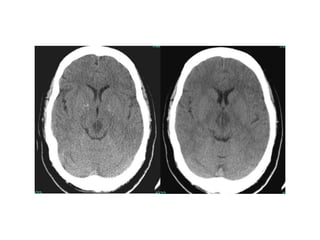

CT SCAN OF BRAIN

Ct scan lecture